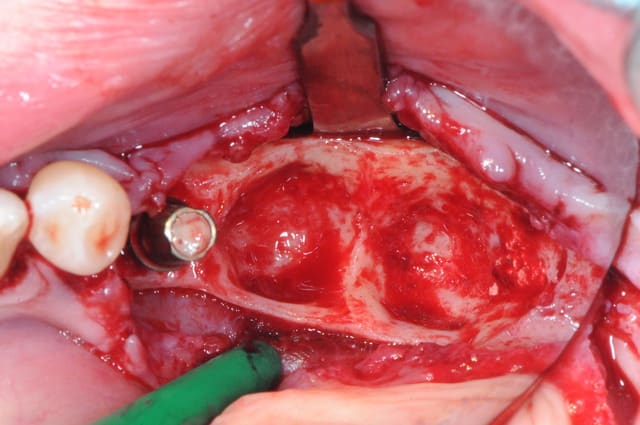

1-2-3 dépose du bridge

facile :) ça vient tout seul.

4 après un long moment de nettoyage, de curetage, de surfaçage implantaire, d'aeropolissage de l'implant, etc...

on fini enfin par arriver à ça.

ah oui, j'ai passé 2 fois un bon gros quart d'heure à gérer deux petites artères intra-osseuses de me..e qui m'ont vraiment pourri ma zénitude per-op.

de vraies petits geysers! ça doit faire dix ans que j'en avais pas eu des comme ça.

2-3 l'implant 35 que j'ai décidé de garder et donc de nettoyer.

pour le nettoyage, j'ai utilisé, en plus de l'aéropolissage, un écouvillons de chez STRAUMANN en titane.(à mon avis beaucoup trop souple et trop long.

y en a qui connaissent ?)